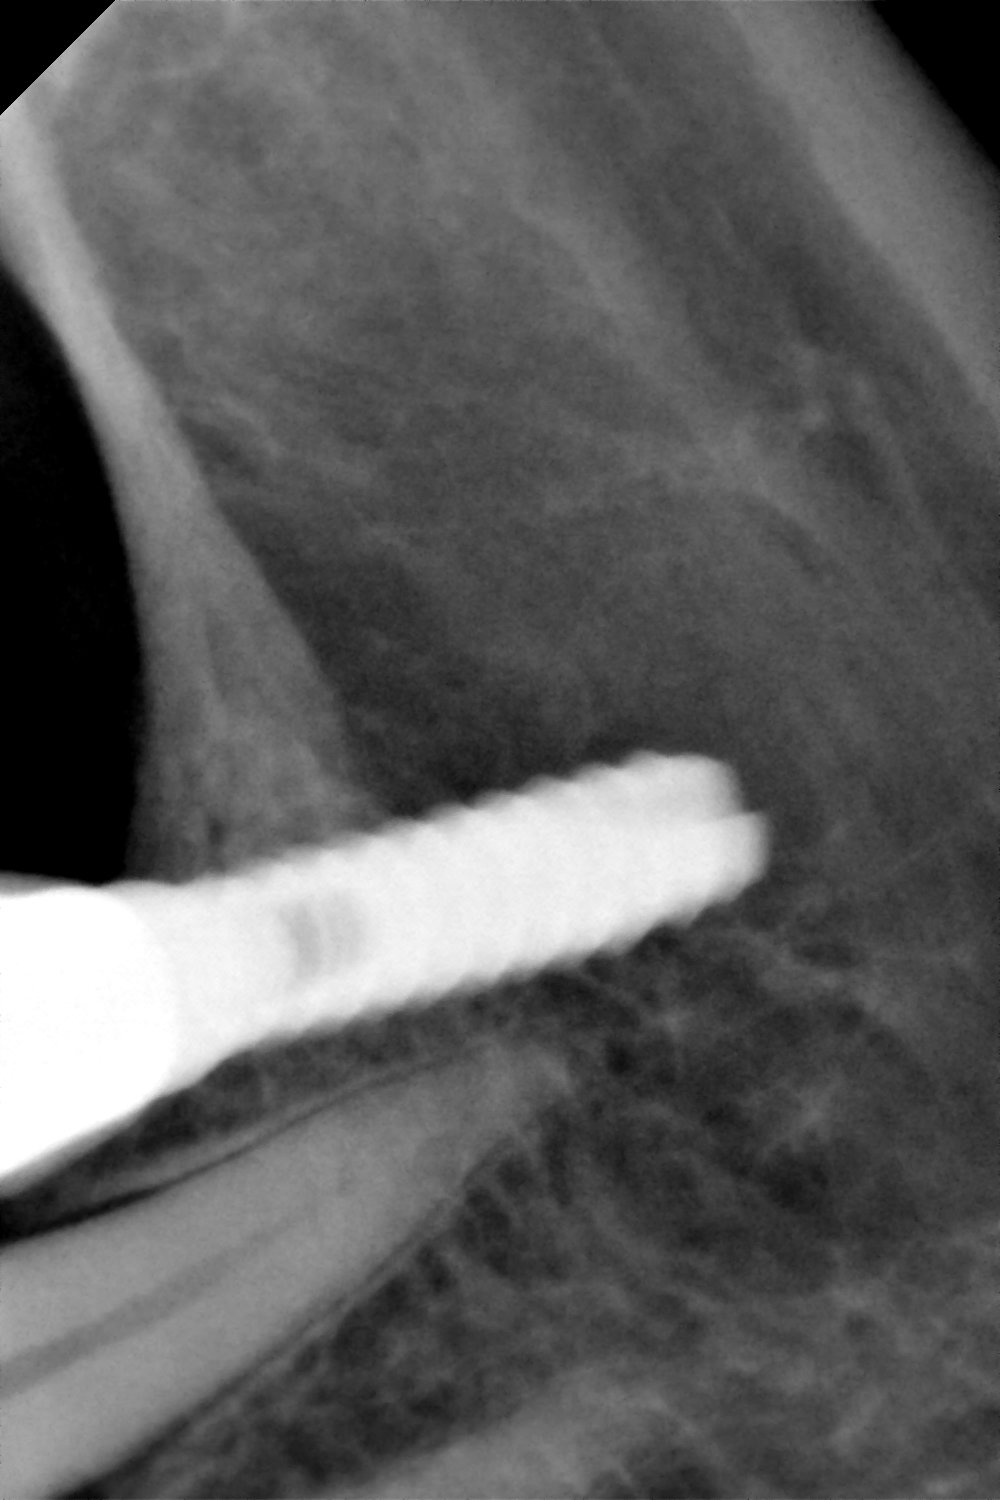

Hola, buenas tardes Tengo esta paciente con un implante en posición de 37 que nunca fue rehabilitado, quiere hacerse prótesis y no sabe qué implante es. Agradezco la ayuda enormemente [...]

Buenas tardes, necesito cambiar el implante de la pieza 16 pero no sé su marca ni su medida, ¿ podeis ayudarme?